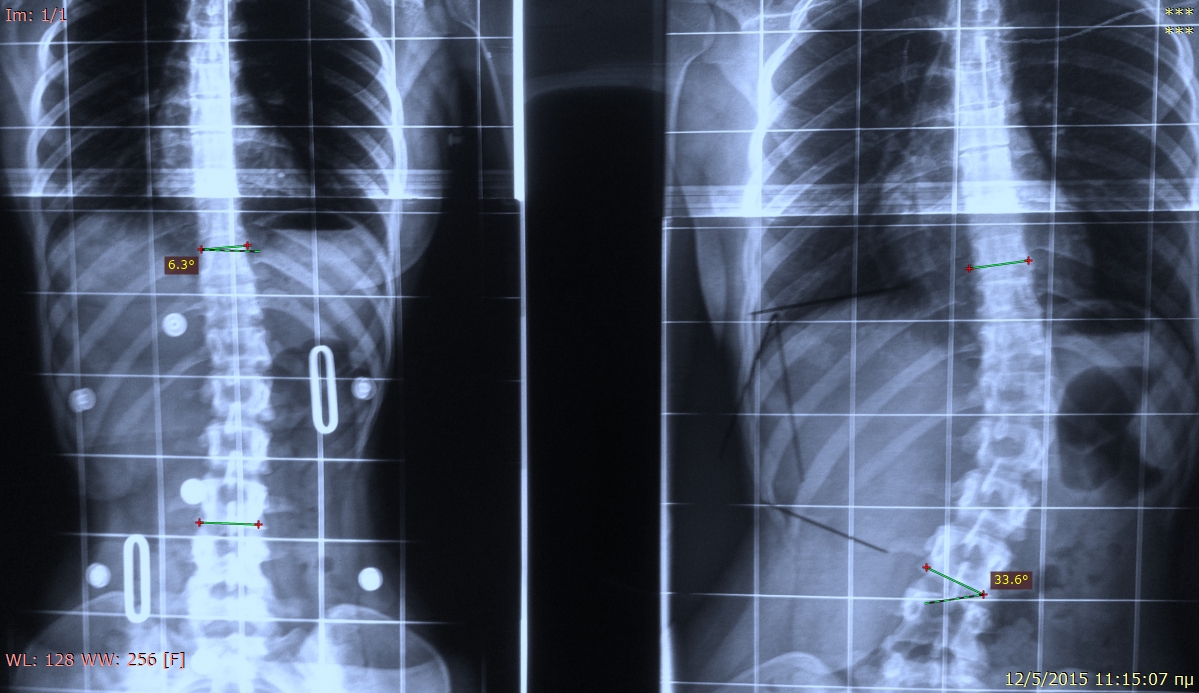

La scoliosi è una deformità laterale della colonna vertebrale che può insorgere durante l'infanzia e l'adolescenza.

Uno dei segni più evidenti di scoliosi nei bambini è la curvatura laterale della colonna vertebrale. Questa curva può essere osservata anche a occhio nudo, specialmente quando il bambino è in piedi o in posizione eretta.